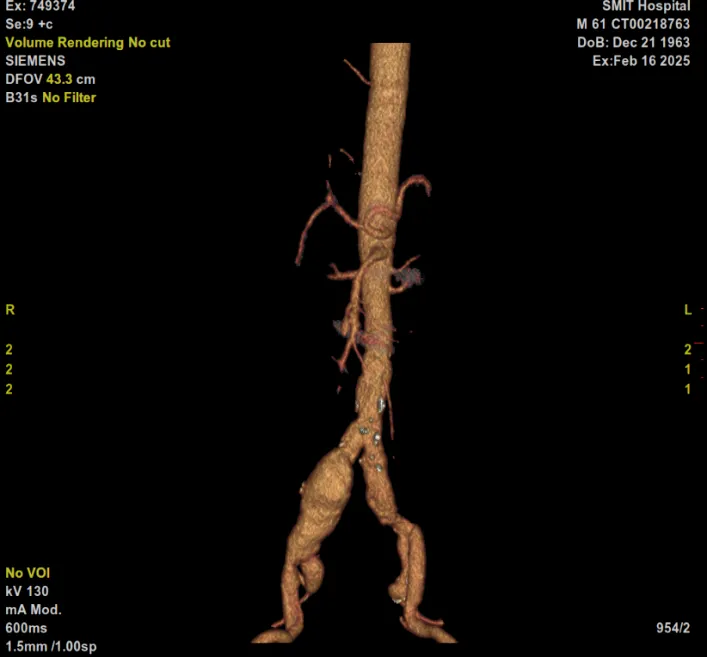

据悉,61岁的李爹爹来院就诊,经检查确诊为腹主动脉夹层合并髂动脉瘤,并伴有瘤壁血栓,病情危重,随时可能危及生命。面对如此复杂的病例,医院高度重视,立即组织心血管病科、普外科、麻醉科、医学影像科等多学科专家进行会诊。专家团队仔细分析患者病情,充分评估手术风险,最终制定了详尽的手术方案和应急预案。

在上级教授的指导下,夏贤龙副主任介入团队凭借精湛的技术和默契的配合,成功为患者实施了腹主动脉髂动脉覆膜支架植入及右侧髂内动脉瘤栓塞术。手术过程顺利,患者术后恢复良好,目前已康复出院。